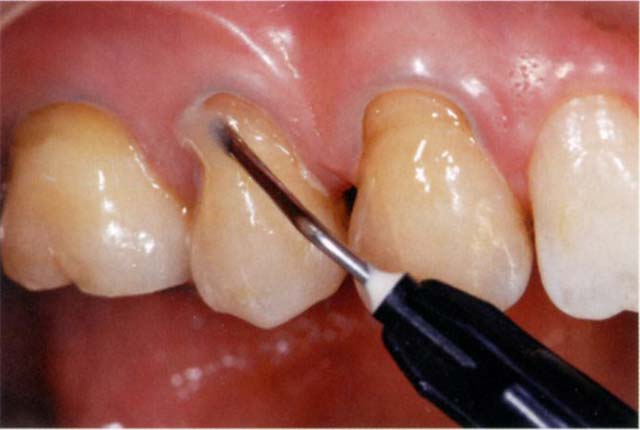

審美面でも築盛でも有益なレイヤリングテクニック

筆者は楔状欠損の治療を行う際、ほとんどの場合レイヤリングテクニック(積層充填法)を用いている。これは、ベースに通常のシェード、表層にやや明るめのシェードを用いることで色に深みがでてより自然に見えること、そして、フロアブルレジンの場合は表面張力を利用して築盛するので、充填部の表面がより平滑であるほうが成形しやすいことが主な理由である。また、ジメタクリレートポリマーの導入により、歯質に適合しやすいながらも垂れにくいという操作性の高さもその理由である。図Bは90°に立てかけてあるアクリル板に最深部で2mm、直径5mmの穴をあけ、そこにフィルテック™シュープリームフローコンポジットレジンを築盛し3分間放置したものである。平面部にも同様にする。その結果、平面部に築盛したほうがより自然な歯頸部からの立ち上がりを成形できていることがわかる。つまり、楔状欠損、V級窩洞ともに、あらかじめ下地を平面にしていたほうが成形しやすいのである(図C)。